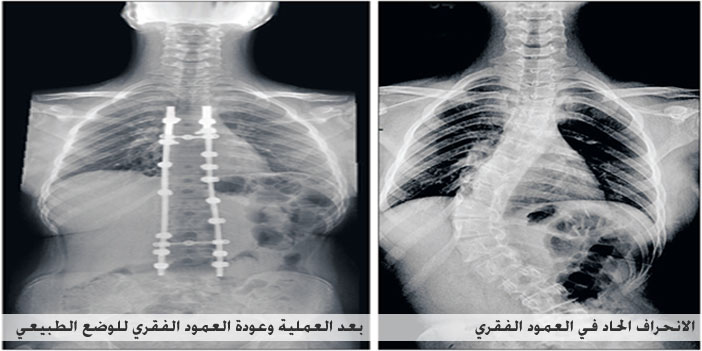

نجح فريق جراحة العظام والعمود الفقري بالمجمع الطبي بالعليا التابع لمجموعة د. سليمان الحبيب الطبية في إجراء عملية جراحية دقيقة وناجحة لتعديل اعوجاج بالعمود الفقري، تبلغ نسبته 70 %، نتج منه تشوه خِلقي لطفل يبلغ من العمر 4 سنوات، كان يعاني صعوبة في عملية التنفس، واعوجاجًا حادًّا بالرقبة.

وأضاف بأنه تم استقبال الطفل بالعيادة، ودراسة حالته الصحية جيدًا، وعمل الفحوصات التشخيصية اللازمة بالتحاليل المخبرية، وإجراء التصوير المقطعي (C.T. Scan) والرنين المغناطيسي (M.R.I) على الفقرات الصدرية، وأظهرت النتائج وجود فقرة غير مكتملة من العمود الفقري الصدري، تقع بين الفقرة العاشرة والحادية عشرة.

واختتم الدكتور أركان حرب قائلاً: إن العملية أُجريت بنجاح تام - ولله الحمد - وتم تحسين استقامة العمود الفقري، واستطاع الطفل المشي والحركة بعد العملية. مشيرًا إلى أن الطفل غادر المستشفى بعد 5 أيام وهو بصحة جيدة، وبدأ يمارس حياته بشكل طبيعي.